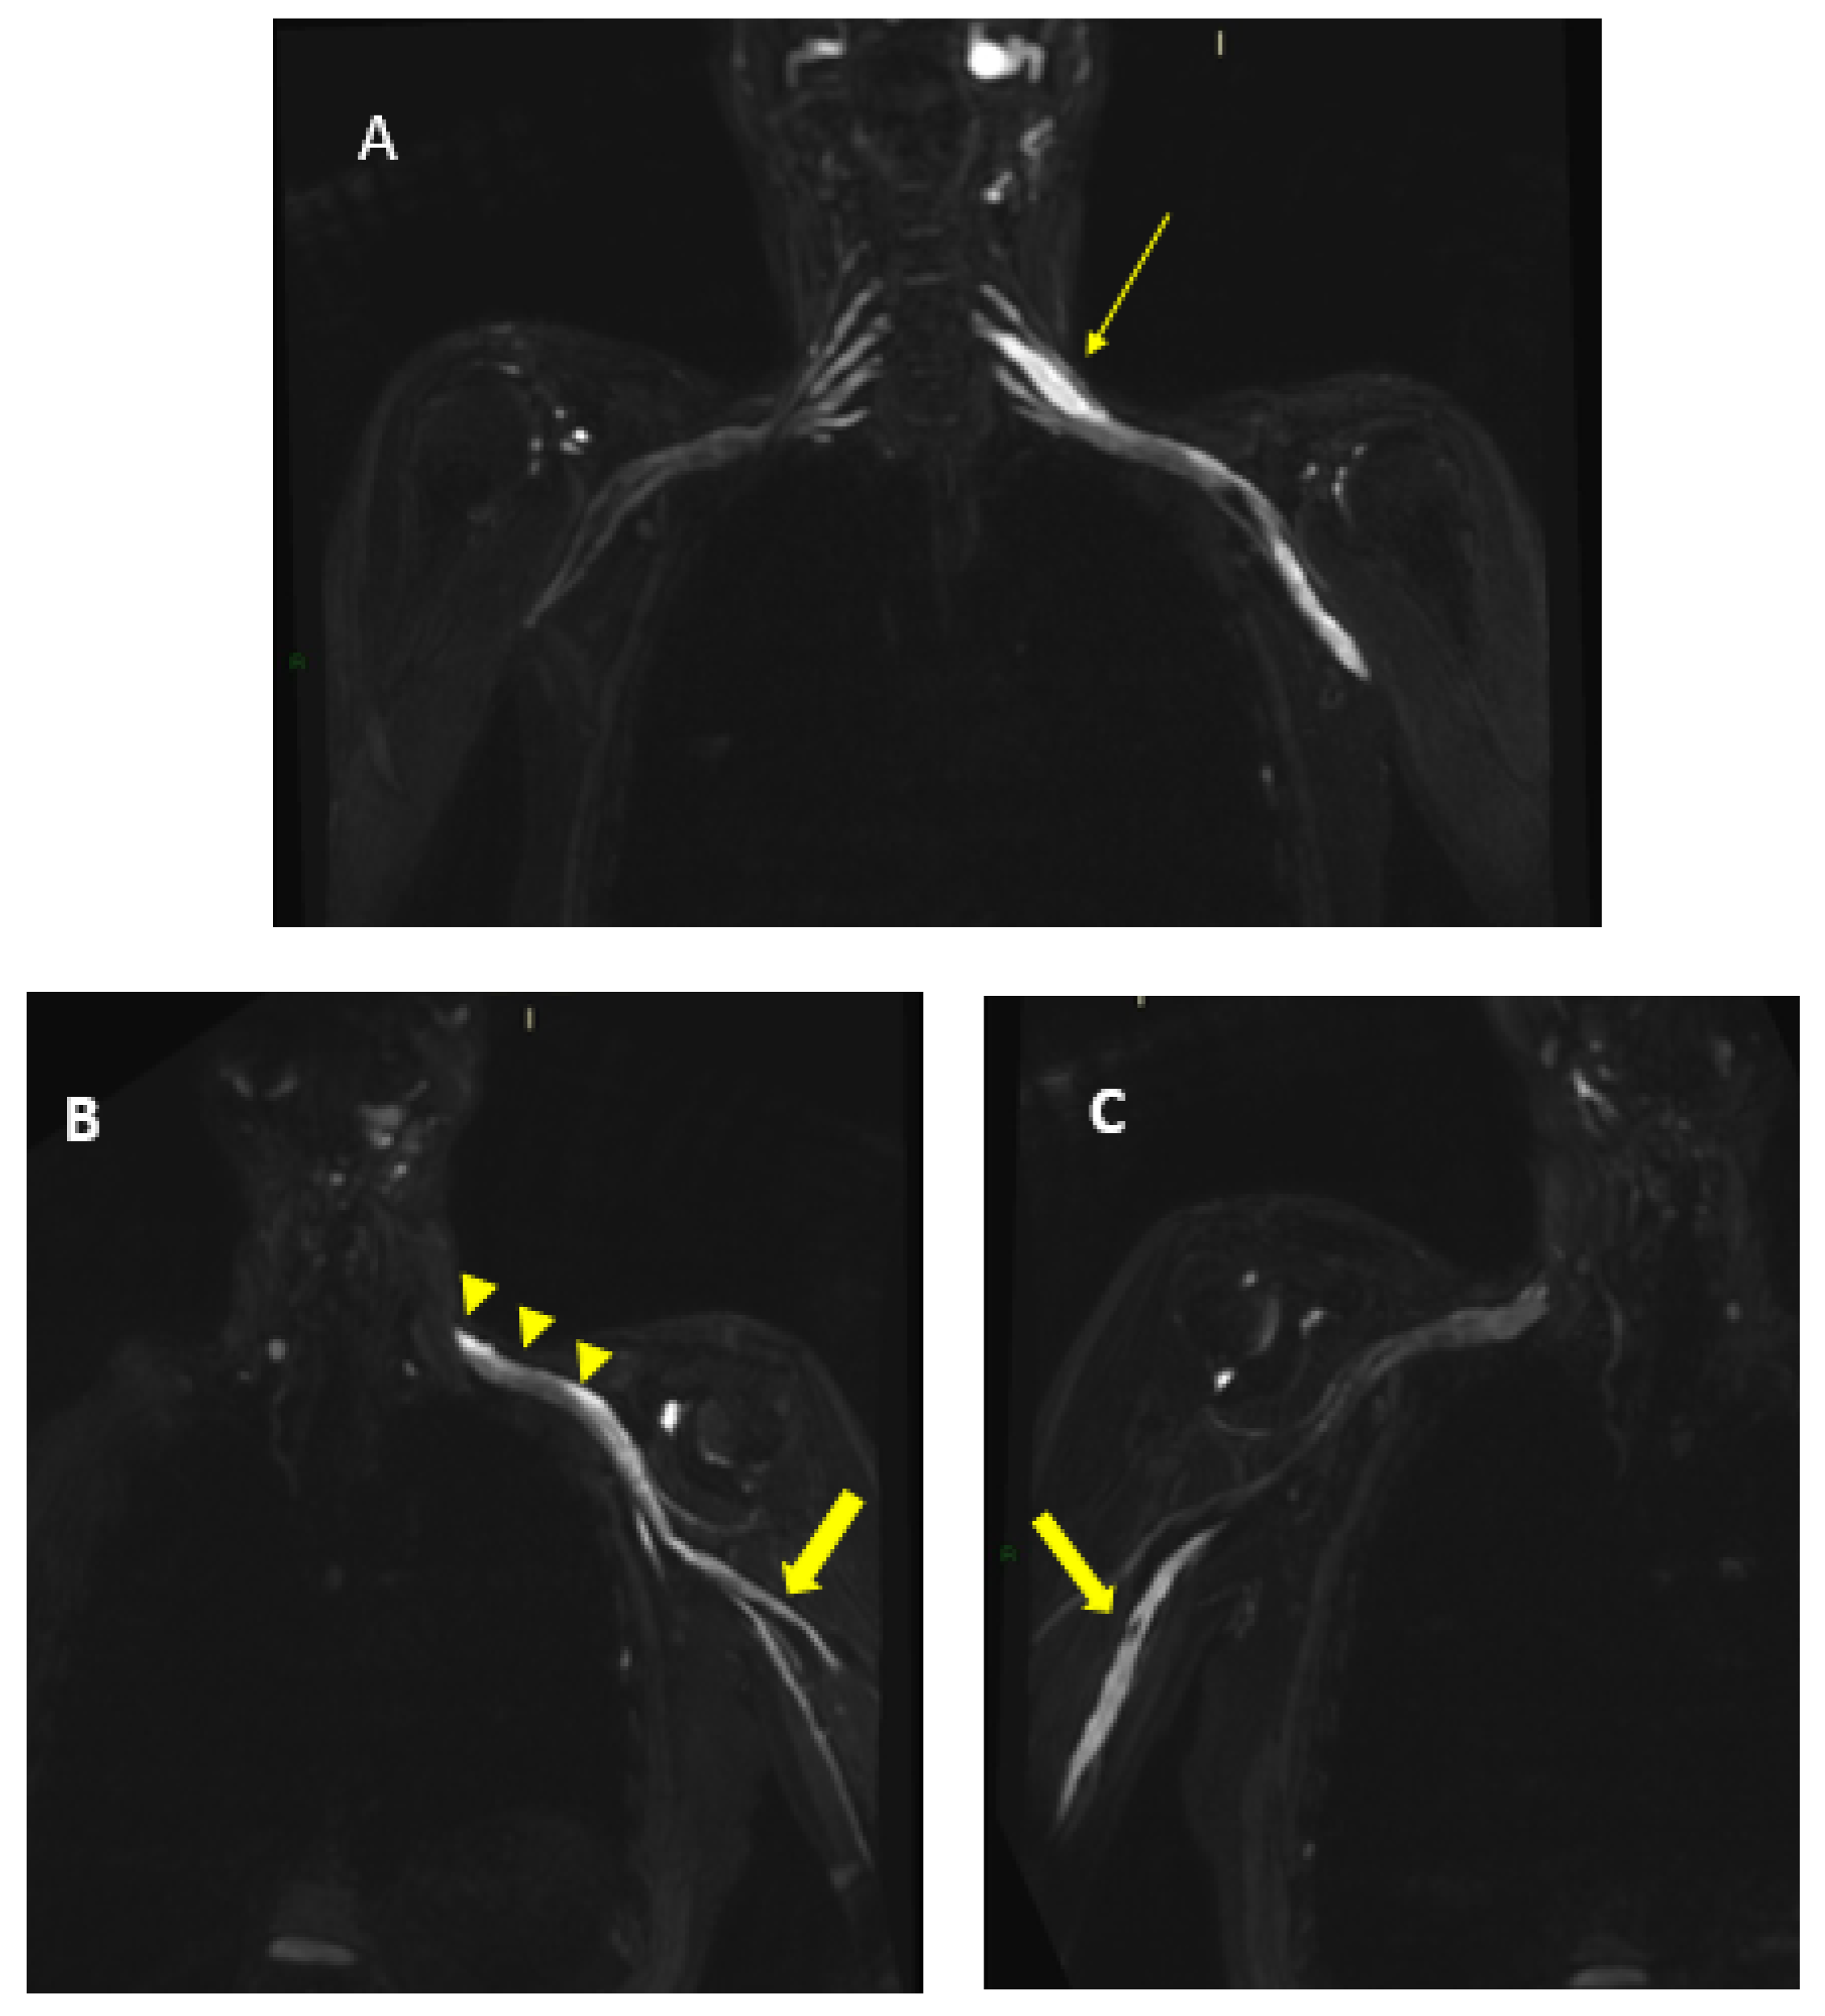

Figure 8.

MIP (Maximum Intensity Projection) reconstructions of the 3D cube nerve-MR sequence of the lumbosacral plexus documented a moderate and diffuse increase in thickness and signal intensity on T2W images of the lumbar and sacral roots; the left S1root (arrows) appears to be pathological (thickened and markedly hyperintense in T2w). Transverse diameter S1 roots (n.v. * 5.27 ± 0.53) left 8.4 mm; right 8.2 mm). * Normal values (n.v.) according to the recent study of Su X et al. [20].